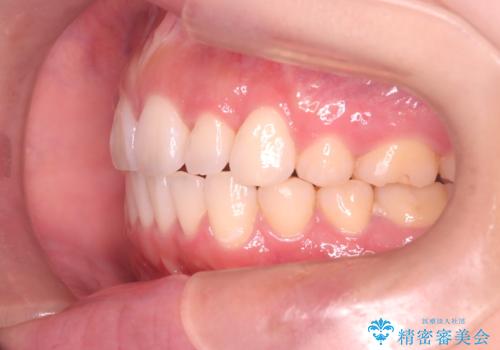

【審美装置】前歯のがたがたを治したい

- 前歯の凸凹と口元の突出感を主訴に来院されました。

臼歯関係が上顎前突傾向のため、上の小臼歯を抜歯してワイヤー矯正を行なっております。

下顎の叢生はIPRを行なって配列しています。